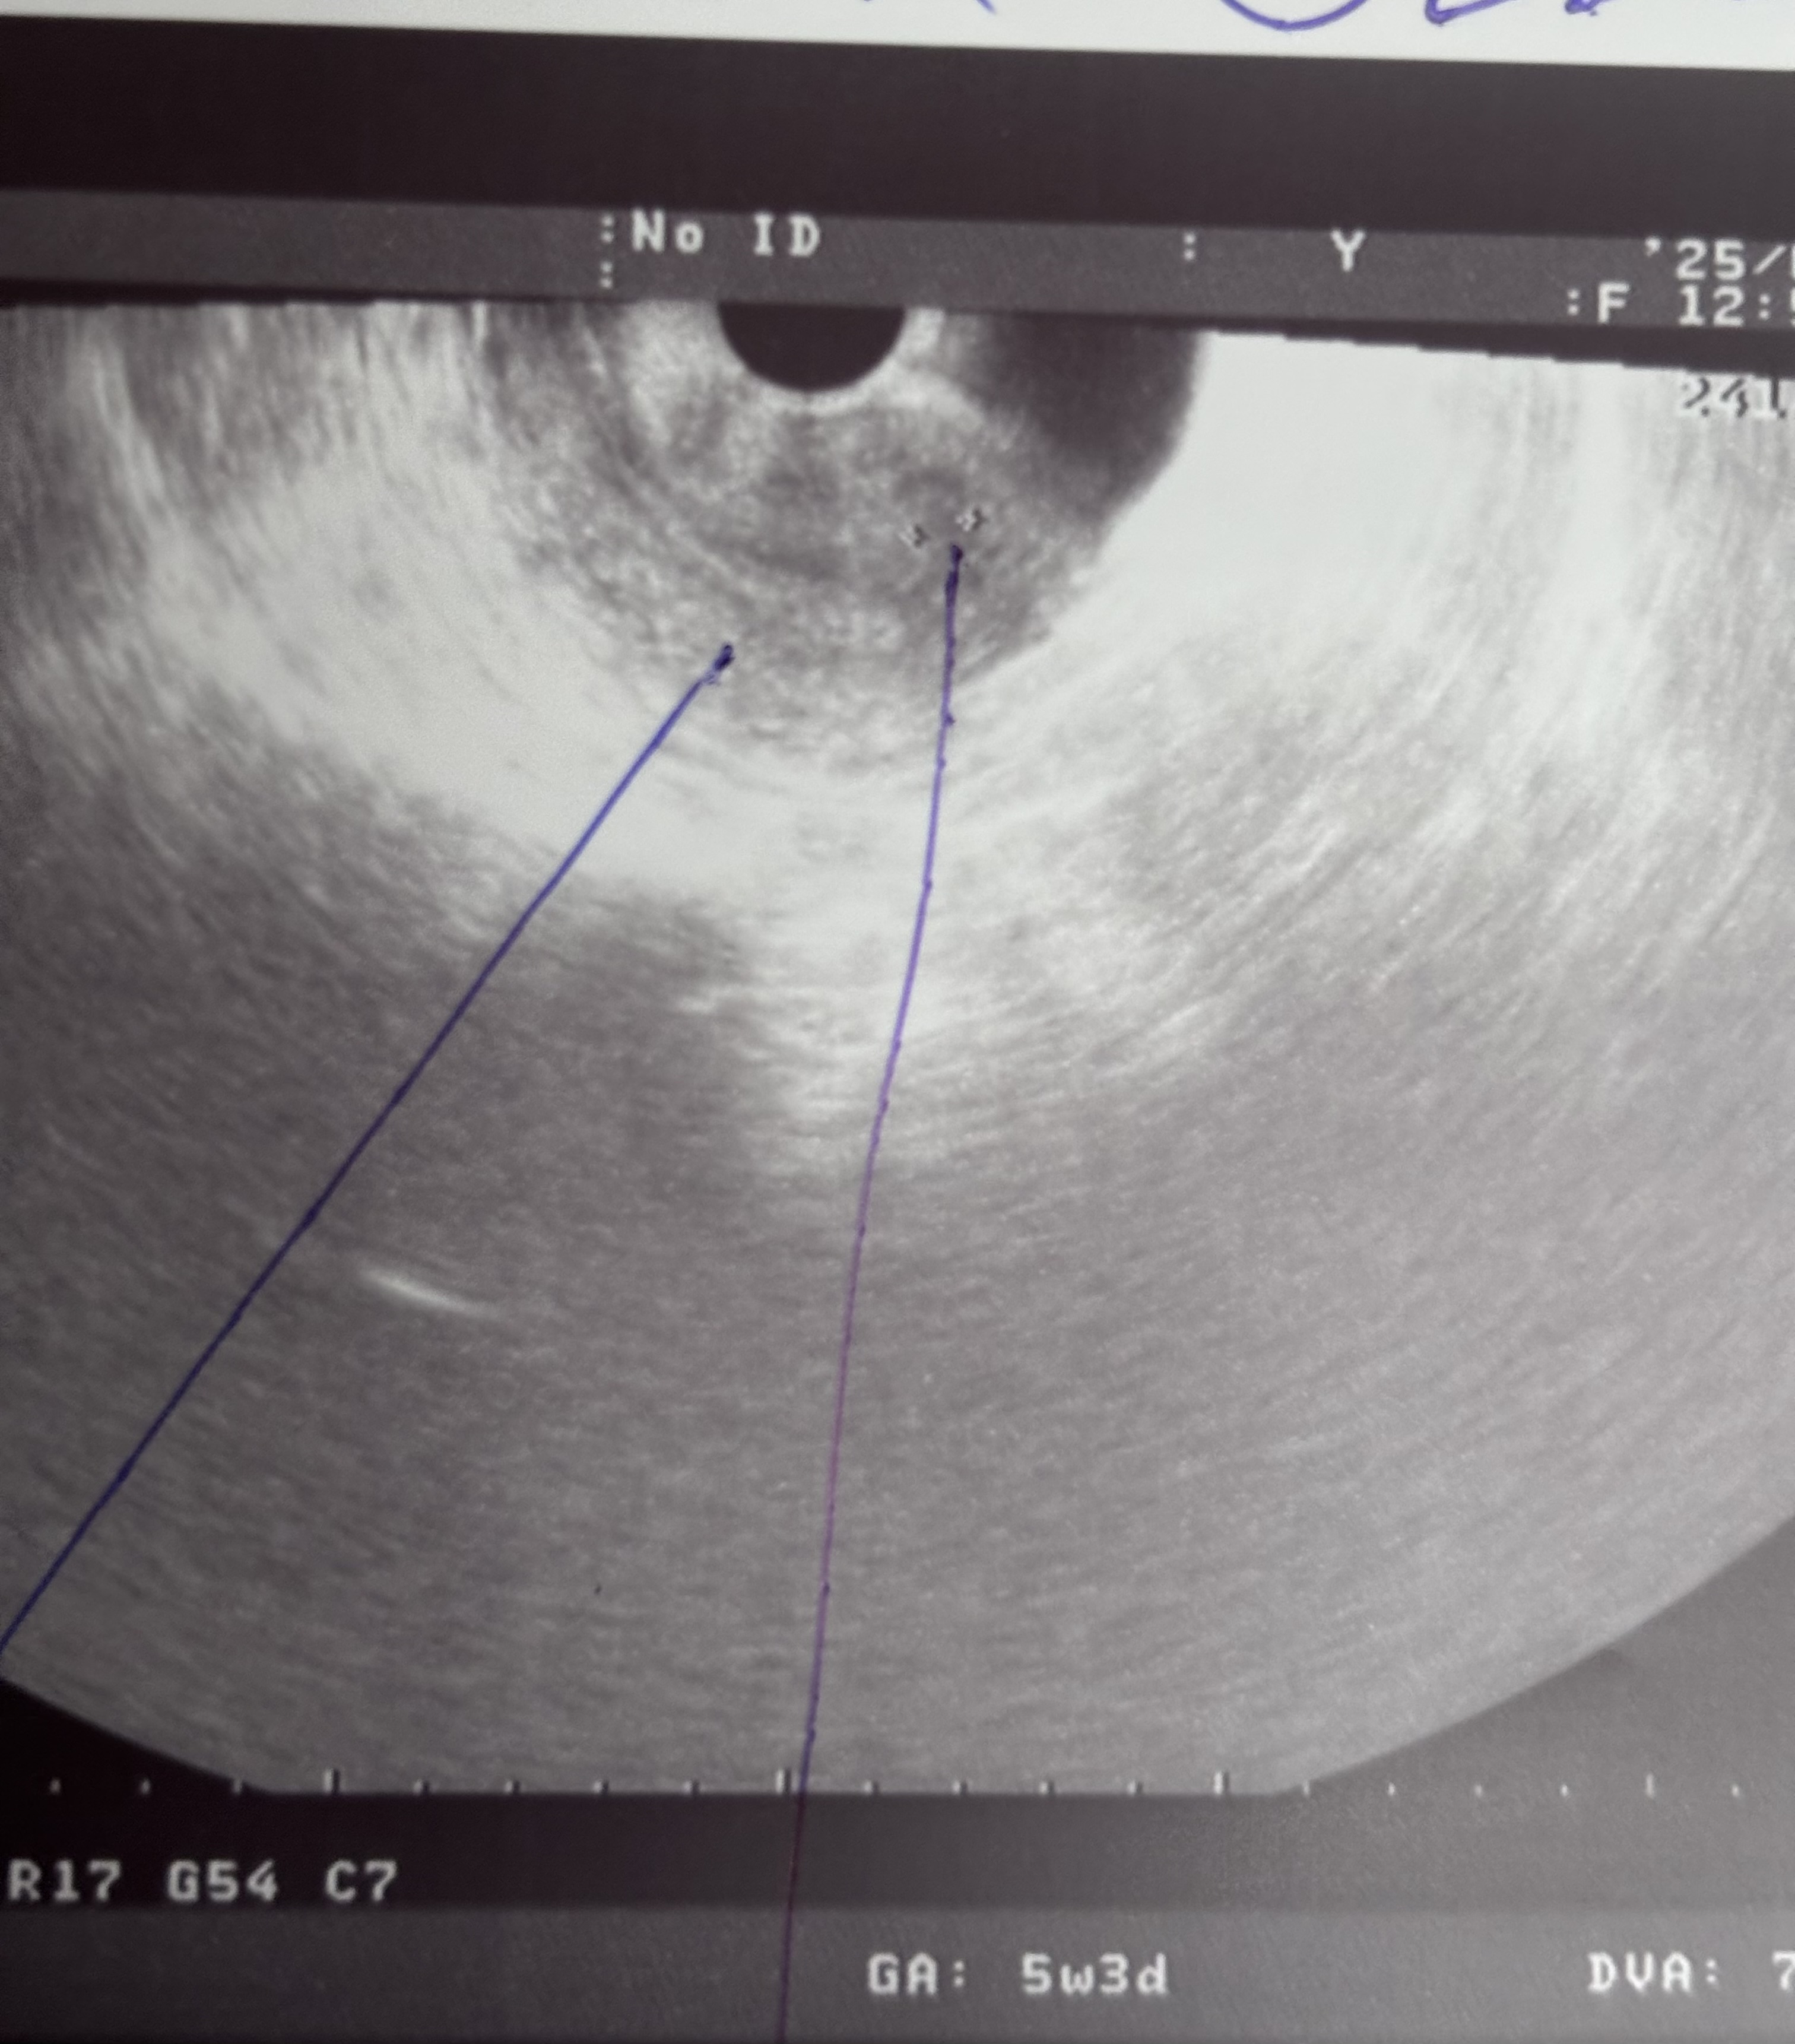

cherry, мне больше интересно есть ли вообще беременность,врач узи полностью ее исключил ,но я перекопала весь интернет и нашла инфу,что это 50/50 Можно увидеть плодное яйцо на 5 неделях уже ,а можно и не увидеть

Аня , что касается узи, вы говорите что у вас 5 недель, но это акушерские недели, судя по тому что у вас только начала появляться вторая полоска на тестах (типа 7 дней задержки), у вас была поздняя овуляция

Аня , к слову, тесты начинают полосатить примерно через 10 дней после зачатия, то есть у вас эмбриональных недель 2 полных от силы